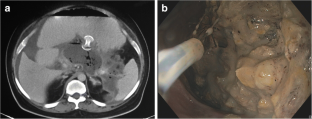

Fig. 1